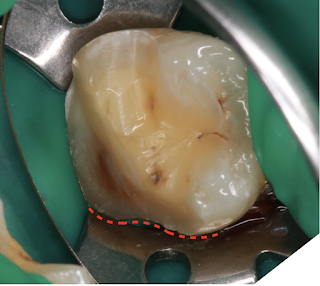

遠心的交界面幾乎沒入牙齦下

頰側觀:

與牙套的製備方式相比,可保留較多的齒質

補充說明:這個舌側的S型曲線是來自於下顎第二大臼齒雙牙根的型態,這也是這個病例中,直接樹脂復形最難處理得完美的位置